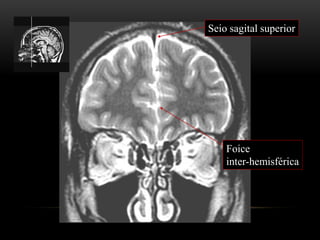

Foice

inter-hemisférica

Seio sagital superior